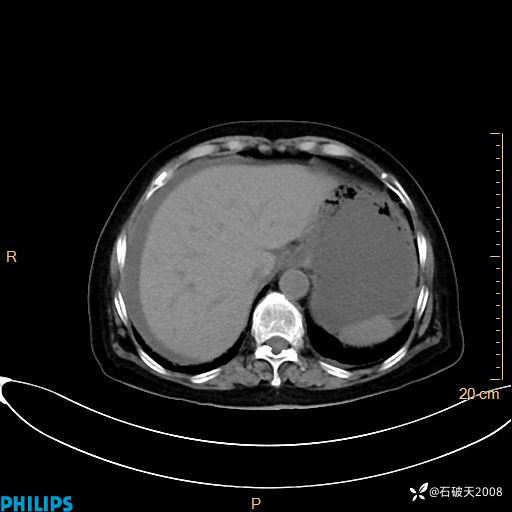

静脉期